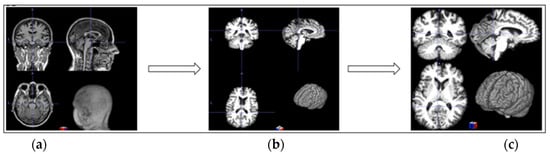

3.2. MRI Preprocessing

- Motion correction corrects minor head movements that may occur during head scanning. It ensures that all slices in one scan are aligned.

- Skull stripping removes all non-brain tissues from MRI scans to isolate the brain, which is a crucial step for AD classification.

- Intensity normalization adjusts the intensities of MRI voxels to a standard range to enhance the contrast and consistency in the images.

- For background removal, we cropped the background to eliminate most of the non-brain elements.